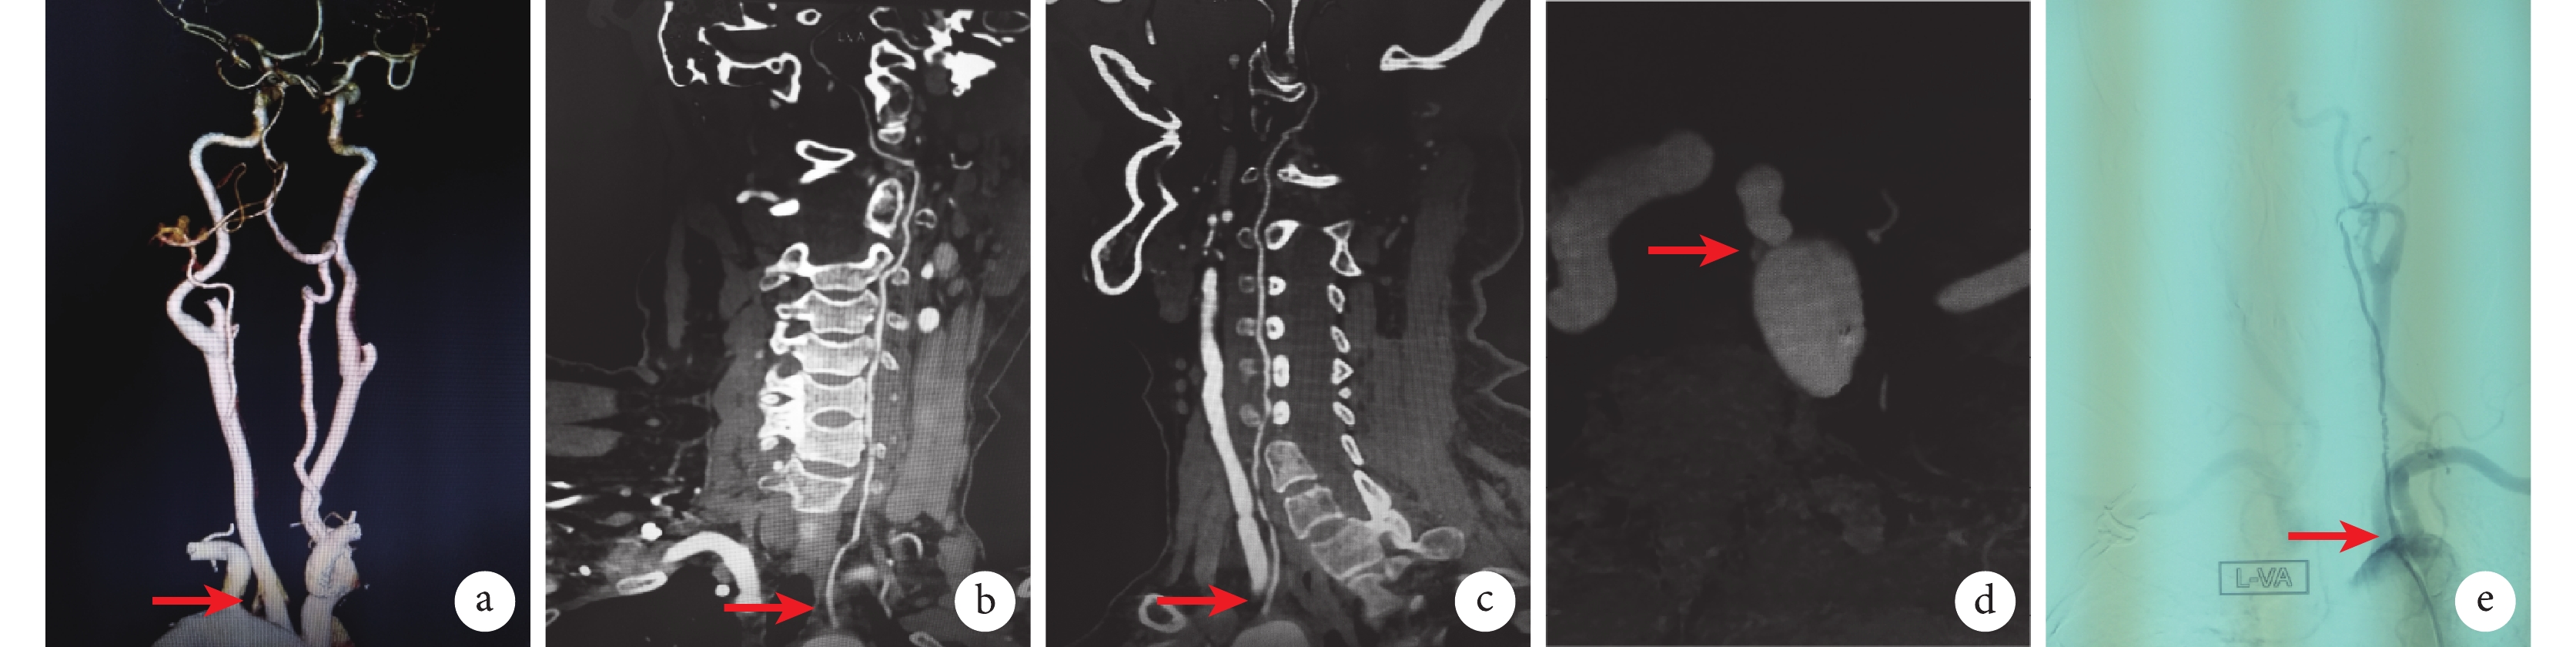

術前充分評估椎-基底動脈的血流情況,確認優勢側椎動脈。超聲和CT血管造影(CT angiography,CTA)顯示左椎動脈口嚴重狹窄(70%~99%)和主動脈弓異位起源(圖1a~1d)。

圖1

示起自主動脈弓的椎動脈CTA檢查結果及支架置入

a~d:分別為CTA三維重建(a)、冠狀位(b)、矢狀位(c)及軸位(d)掃描結果,左椎動脈起始部重度狹窄并異位起源于主動脈弓 (紅色箭頭);e:數字減影血管造影顯示左椎動脈支架置入情況(紅色箭頭)

① 局部麻醉滿意后,采用Seldinger技術逆行穿刺右股總動脈,置入8 F(Introducer Ⅱ,Terumo)動脈鞘,通過動脈鞘給予肝素(50 U/kg,華北制藥股份有限公司),根據手術時間每超過1 h建議追加注射2 000 U肝素。② 豬尾導管主動脈弓部造影確定病變椎動脈,路圖模式下應用V18導絲 [0.018 in(1 in=0.025 4 m)、300 cm長,Radifocus,Terumo,Tokyo,日本]導引5 F椎動脈導管超選入病變椎動脈,經導管行血管造影,證實病變椎動脈重度狹窄。③ 沿V18導絲將同軸的多功能導管MPA1及Guiding導管送至椎動脈開口處(Guiding導管連接Y形閥,接沖洗鹽水,充分排氣后將多功能導管插入Guiding導管內形成同軸導管)。撤出多功能導管,再次行椎動脈血管造影確定病變部位并測量正常椎動脈直徑,沿著導絲進入球擴支架(直徑4~5 mm,波科Express,SD)充分擴張狹窄處椎動脈,擴張時間6~8 s,充氣壓力為 8 atm(1 atm=101.325 kPa)。④ 擴張后造影評估狹窄段<30%殘余狹窄,并且無限制血流的夾層、無椎動脈栓塞、無造影劑外溢,術中所有病例的椎動脈血流通暢,未發現夾層及遠端栓塞,大腦后循環顯影良好,無造影劑外溢。⑤ 最后以血管縫合器縫合右股動脈穿刺點,加壓包扎。經數字減影血管造影證實椎動脈狹窄消失,狹窄<30%,無血管破裂及遠端栓塞(圖1e)。術中操作輕柔,提高導管及導絲操作的熟練水平,術中導絲盡量繞開斑塊,避免椎動脈不必要的栓塞。